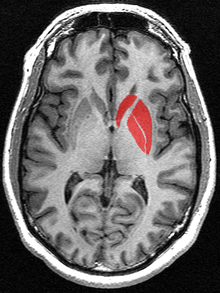

Huntington’s disease (HD) is an inherited disorder that causes progressive degeneration of neurons within the cerebral cortex and striatum of the brain (OMIM 143100) resulting in loss of motor functions (involuntary muscle contractions), decline in cognitive ability (eventually resulting in dementia), and changes in behavior (Urdinguio et al., 2009).

Huntington’s is caused by an autosomal dominant mutation expanding the number of glutamine codon repeats (CAG) within the Huntingtin gene (Htt)(OMIN 613004) (http://www.omim.org/entry/143100). The Htt gene encodes for the huntingtin protein which plays a role in normal development but its exact function remains unknown (Nasir et al., 1995). The length of this CAG repeat correlates with the age-of-onset of the disease. The average person without Huntington’s has less than 36 CAG repeats present within the Htt gene. When this repeat length exceeds 36, the onset of neuronal degradation and the physical symptoms of Huntington’s can range from as early as 5 years of age (CAG repeat > 70) to as late as 80 years of age (CAG repeat < 39) (Chen et al., 2002).

This CAG expansion results in mRNA downregulation of specific genes, decreased histone acetylation, and increased histone methylation (Ryu et al., 2006; Hazeki et al., 2002). The exact mechanism of how this repeat causes gene dysregulation is unknown, but epigenome modification may play a role. For early-onset Huntington's (ages 5–15), both transgenic mice and mouse striatal cell lines show brain specific histone H3 hypoacetylation and decreased histone association at specific downregulated genes within the striatum (namely Bdnf, Cnr1, Drd2 - dopamine 2 receptor, and Penk1 - preproenkephalin) (Sadri et al., 2007). For both late- and early-onset Huntington’s, the H3 and H4 core histones associated with these downregulated genes in Htt mutants have hypoacetylation (decreased acetylation) compared to wild-type Htt (Hazeki et al., 2002; Sadri et al., 2007). This hypoacetylation is sufficient to cause tighter chromatin packing and mRNA downregulation (Hazeki et al., 2002).